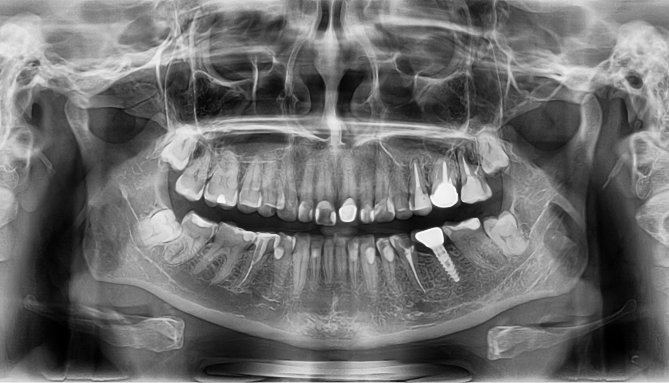

一、全景片

主要睇下有冇蛀牙、智齒、埋伏牙、多生牙等牙齒異常嘅問題,仲有睇下唔唔正常嘅關節、有冇牙根/牙槽骨吸收等情況有無。